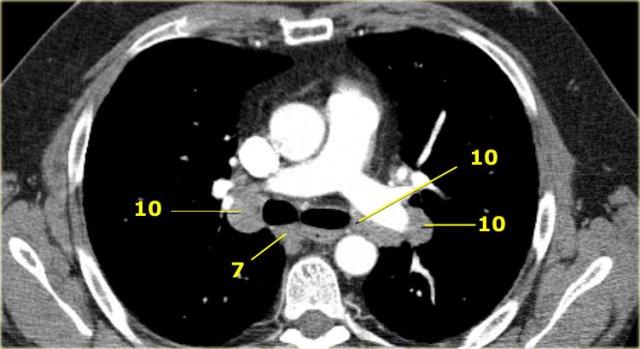

Hạch rốn phổi, thùy phổi và (phân) phân thùy nhóm 10-14

Tất cả các hạch này đều thuộc nhóm N1.

10. Hạch rốn phổi

Bao gồm các hạch tiếp giáp với phế quản gốc và các mạch máu rốn phổi.

Bên phải, trải dài từ bờ dưới tĩnh mạch đơn đến vùng gian thùy.

Bên trái, từ bờ trên động mạch phổi đến vùng gian thùy.

7. Hạch dưới carina

Các hạch này nằm ở phía dưới carina khí quản, nhưng không liên quan đến phế quản thùy dưới hoặc các động mạch trong phổi.

Bên phải, chúng trải dài xuống đến bờ dưới phế quản trung gian.

Bên trái, chúng trải dài xuống đến bờ trên phế quản thùy dưới.

Bên trái là hạch dưới carina nhóm 7 nằm bên phải thực quản.

Hạch rốn phổi là các hạch thùy gần, nằm ở phía xa so với nếp gấp màng phổi trung thất và các hạch kề phế quản trung gian bên phải.

Các hạch từ nhóm 10 đến 14 đều là hạch N1, vì chúng không nằm trong trung thất.